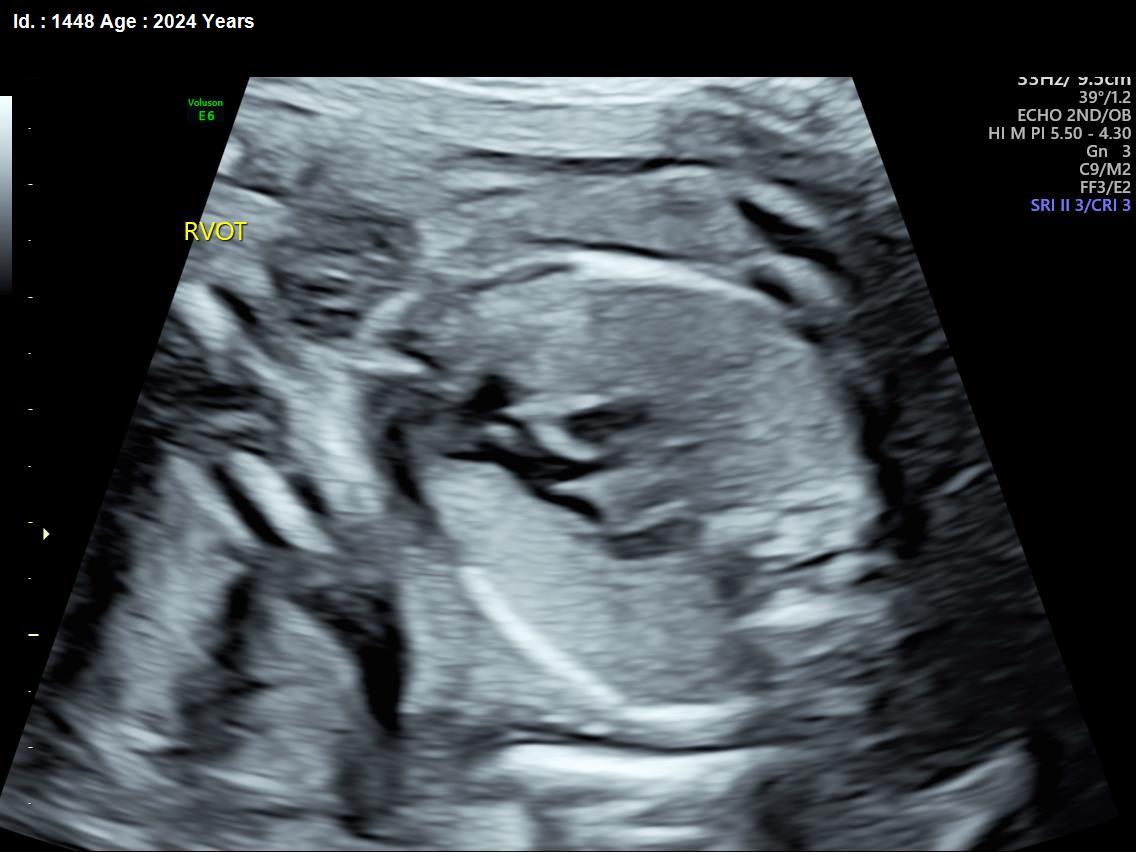

It is a test similar to ultrasound. It allows the doctor to see structure and function of the baby’s heart in detail. It also enables the doctor to see blood flow through fetal heart and cardiac rhythm. The scan is done by a radiologist or a fetal medicine specialist.

A fetal echocardiogram focuses specifically on the fetal heart, providing a detailed examination of its structure and function. In contrast, a standard ultrasound assesses overall fetal development and growth.